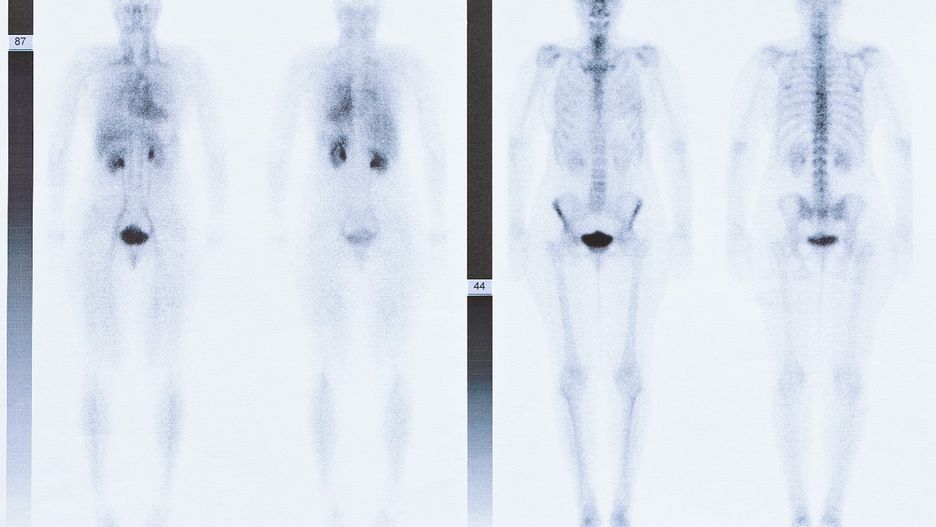

Scyntygrafia kości jest pomocna przy ocenie stanu czynnościowego kości i stawów. W trakcie trwania tego badania do organizmu wprowadzane są małe ilości izotopów promieniotwórczych - radioznaczników, które osadzają się w miejscach podwyższonego metabolizmu tkanki kostnej. Radioznaczniki gromadzą się głównie w miejscach intensywnego rozpadu kości oraz w miejscach, gdzie toczy się proces zapalny. Istnieje także możliwość uwidocznienia w badaniu scyntygraficznym obrzęku tkanek sąsiadujących z kością.

W porównaniu do badania radiologicznego scyntygrafia kości wykazuje się o wiele wyższą czułością w stosunku do ujawnienia ognisk rozpadu kości. Dodatkowo badanie scyntygraficzne może być pomocne w diagnostyce stanów zapalnych, oceny ukrwienia koścca oraz obrzęku tkanek miękkich. Dzięki scyntygrafii kości możliwe jest różnicowanie stanów zapalnych tkanki kostnej oraz procesów nowotworowych.